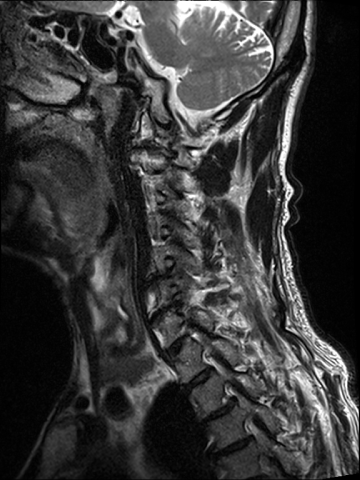

경추 협착증 수술 전·후

2023.03.07

2023.03.13

ㆍ환자 동의를 받은 자료이며, 이미지 사진은 실물과 다를 수 있습니다.

ㆍ모든 자료는 새움병원 자료입니다.